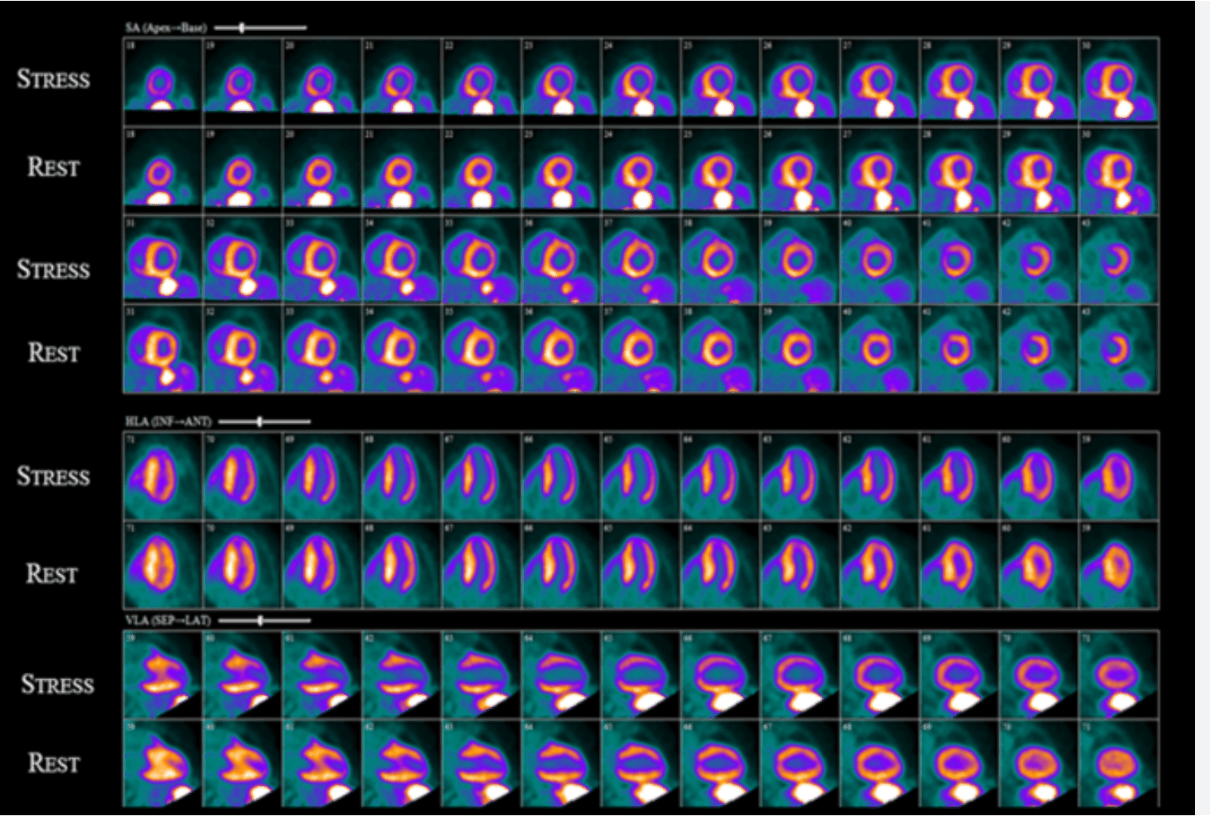

Most striking feature here?

Images showing a small (< 10%) fixed perfusion defect at the apex, moderate (10-20%) ischemia in the territory of the LAD, and mild (< 10%) ischemia in the territory of the LCx. Most striking is the presence of TID with a ratio of 1.41.

There is a large-sized, moderate-intensity, predominantly reversible perfusion defect involving the anterior wall, apex, and septum